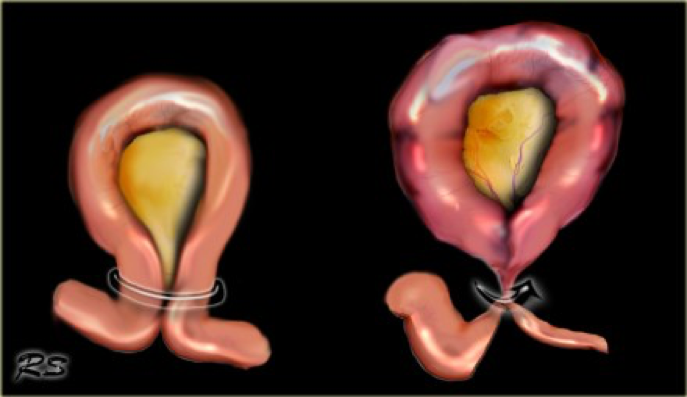

- Whirl sign (volvulus)